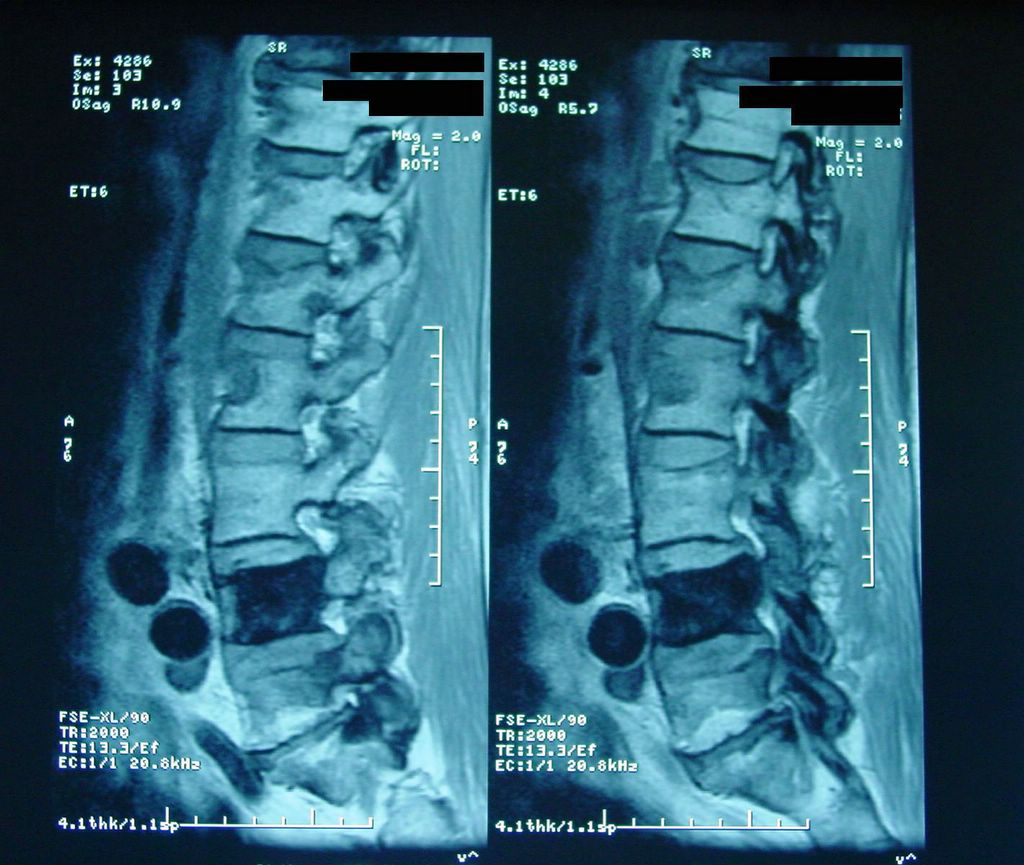

Позвонок Th10: анатомия и фото медицинских иллюстраций